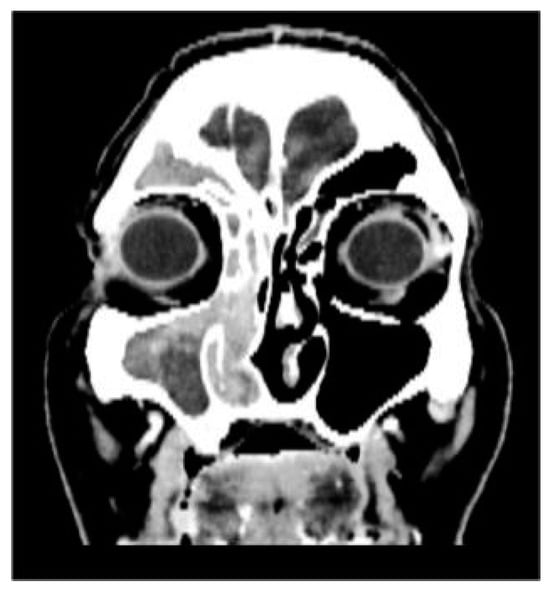

CT showed complete fluid and parafluid accumulation in the right maxillary sinus, with medial sinus wall resorption and antero-lateral walls osteosclerosis, extension of the inflammatory process through the right ostiomeatal complex at the ethmoid cells level as well as at the right frontal sinus level which was completely occupied; this was accompanied by discrete iodophilic right nasal polyposis and thickening of the mucosa at the right sphenoidal sinus level (Figure 2 and Figure 3).

Figure 3.

CT coronal section.